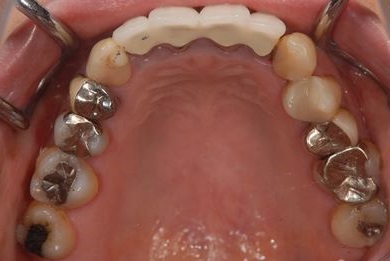

インプラント治療+セラミック治療

| 性別/年齢 | 女性 / 47歳 | ||||||||||||||||||||||||||||||||

| 主訴 | 前歯の黄ばみが気になる。 | ||||||||||||||||||||||||||||||||

| 治療方針 | インプラント・セラミック治療にて、機能的・審美的回復を行う。 | ||||||||||||||||||||||||||||||||

| 治療内容 | インプラント3本、ジルコニアフレームオールセラミッククラウン7本(ジルコニア用土台1本)、メタルボンドセラミッククラウン3本(メタルボンド用土台3本)、ハイブリッドセラミッククラウン3本、ハイブリッドセラミックインレー3本 | ||||||||||||||||||||||||||||||||